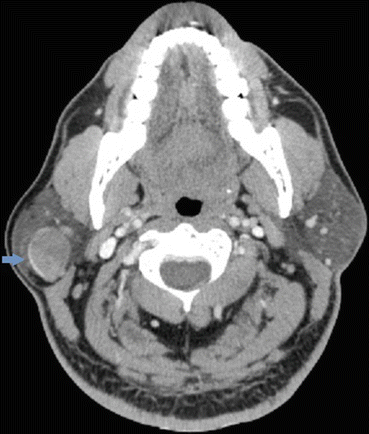

In humans, the two parotid glands are present on either side of the mouth and in front of both ears. As approximately twenty percent of parotid tumors turn out to be cancerous, a mass located near the ear, cheek, jaw, lip or inside the mouth requires immediate medical attention. In humans, the two parotid glands are present on either side of the mouth and in front of both ears. Most parotid tumors are benign with malignancy only comprising approximately 15% to 32%.1 the ct will show bilateral solid and cystic masses involving the parotid glands. Want to learn more about it? Abnormal growths occurring inside the parotid gland are known as parotid gland tumors. Each parotid is wrapped around the mandibular ramus. Most parotid tumors are noncancerous (benign), though some tumors can become cancerous. Salivary gland tumors manifest mainly in the parotid. Plain ct clearly showed parotid tumors in nine of the patients. The salivary glands are classified as major or minor. The parotid gland is the largest of the major salivary glands and the most likely to develop cancer. Approximately 25% of parotid masses are ct scanning provides better detail of the surrounding tissues, whereas mri demonstrates the mass in greater contrast than a ct scan.